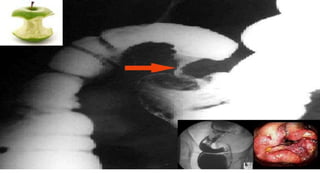

Tumores

Câncer de Cólon é um tumor maligno do intestino

grosso. Na maioria dos casos, na fase inicial não

apresenta sintomas e sua detecção precoce através da

colonoscopia pode proporcionar a cura desta doença.

Algumas vezes o paciente pode apresentar sangramento

nas fezes ou pelo reto, alteração do ritmo intestinal e

ainda alteração do aspecto das fezes, o que pode ser um

sinal de alerta para que o paciente procure um

atendimento especializado.

Mordida da maça